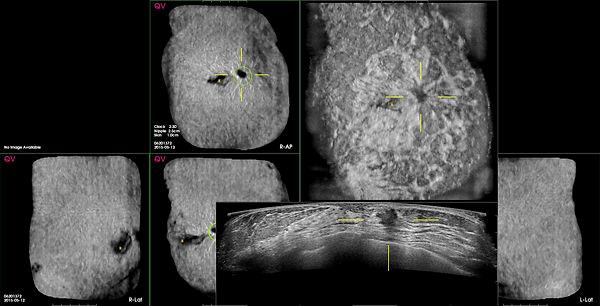

2) Hover Mode enables the user to quickly review a localized area of a view by displaying the corresponding original ABUS Coronal and Transverse images adjacent to the CAD Navigator Image for the point where the cursor is hovering. The Hover Mode activates when the cursor is paused over any area of a CAD Navigator Image hover over abnormality.